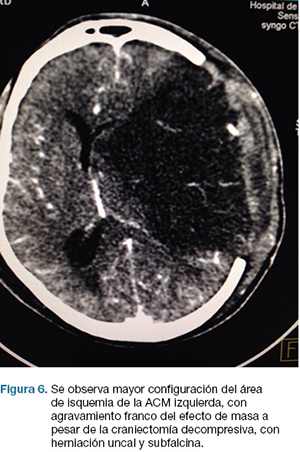

Se realiza TC de cráneo (Figura 4) y rTPA i/v. TC cráneo de control a las 24 hs sin cambios. A las 48 hs instala agravación del nivel de conciencia, apertura ocular al llamado, CGS: 9. Se repite TC cráneo (Figura 5), realizándose hemicraniectomía decompresiva de urgencia. En el post operatorio ingreso a CTI, IOT, en ARM, sin apertura ocular al llamado, gestos, localizando con miembro superior izquierdo. CGS: 8.

En la evolución agrega anisocoria izquierda que revierte con tratamiento médico. TC cráneo de control (Figura 6) evidencia agravación, por lo que se re-interviene realizándose lobectomía temporal izquierda reglada. De la evolución post-operatoria en CTI presenta CGS: 9, cifras de PIC menores de 20 mmHg, pupilas simétricas y reactivas, buena evolución. En sala paciente con mejoría de déficit motor, y de su afasia, emite palabras. Se recoloca hueso al mes de cirugía. Escala mRS al alta: 3.